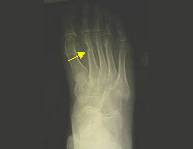

La región del pie está compuesta por huesos y articulaciones con numerosas funciones entre las que destacan el soporte de todo nuestro peso y la función de caminar. Es una región sometida a carga constantemente salvo cuando no caminamos y por ello su rápida recuperación es indispensable para poder desplazarnos de un lugar a otro.El pie a su vez se divide en tres partes: retropié, mediopié y antepié y cada región sufre sus lesiones características. En el deporte las lesiones del pie son muy frecuentes debido a la implicación de éste en la mayor parte de ellos. Son también habituales las fracturas del retropié (calcáneo y astrágalo) en accidentes laborales o precipitaciones donde el paciente cae de pie desde una gran altura. Por lo general las fracturas del pie responden correctamente al tratamiento conservador reservando la actitud quirúrgica a aquellas lesiones complejas irreparables sin cirugía.